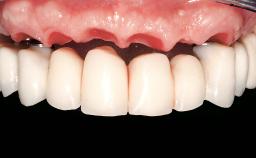

Immediate Loading of Six Implants in the Mandible and Six Implants in the Maxilla and Final Restoration with Full-Arch CAD/CAM Metal Framework FDPs Involving Digital Planning and Guided Surgery

Abutment Type CAD/CAM

Prosthesis Type FDP

Retention Screw-retained, with 4 or more splinted implants Screw-retained, with 4 or more splinted implants